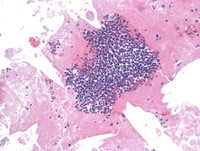

Figure 4: H&E in Primary Effusion Lymphoma

The H&E image of the cell block shows clusters of large atypical plasmacytic cells.